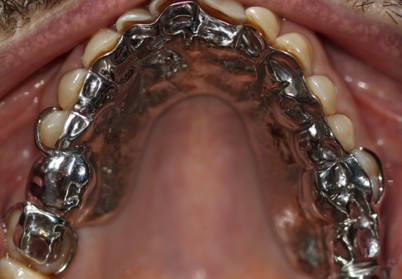

Prosthodontics (also known as dental prosthetics or prosthetic dentistry) is one of the nine dental specialties recognized by the American Dental Association (ADA). Prosthodontists specialize in the diagnosis, restoration, and replacement of missing teeth.

Extensive training and experience give prosthodontists a unique understanding of restoring the dynamics of a smile and healthy mouth with the creation of tooth prostheses. Becoming a prosthodontist requires an additional three years of specialty training after obtaining a DMD (Doctor of Dental Medicine) or DDS (Doctor of Dental Surgery) degree.